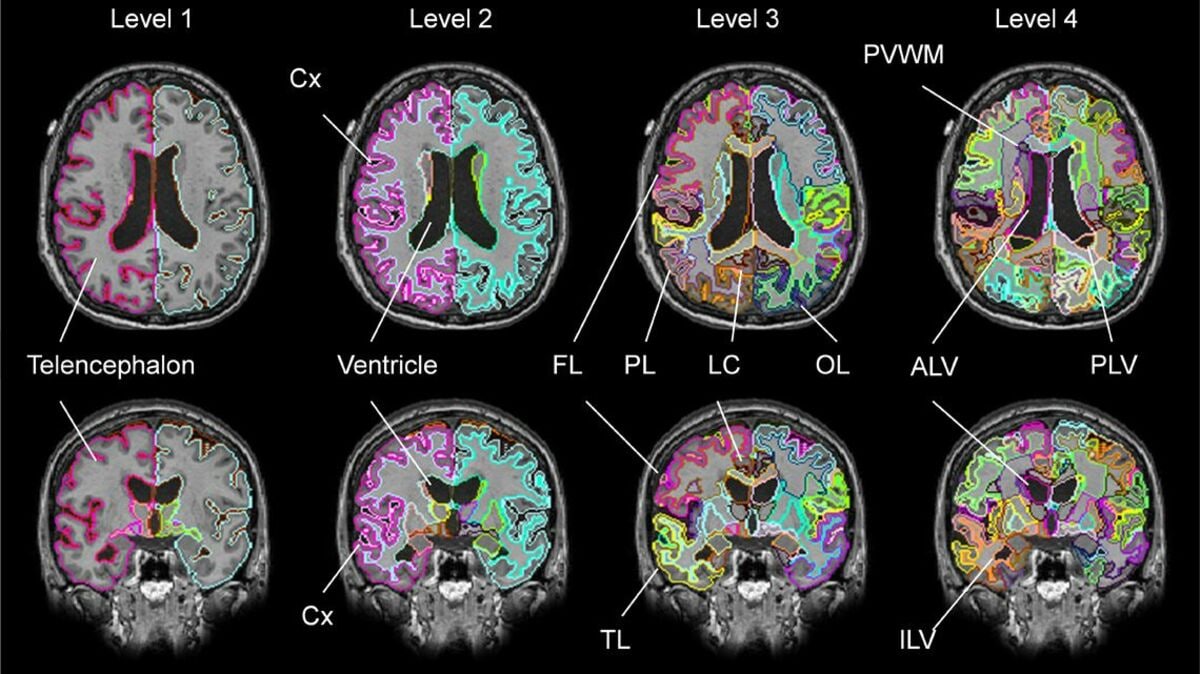

「脳の健康診断」事業に世界に先駆けて挑むのが、アメリカの名門ジョンズ・ホプキンス大学医学部放射線科の教授でもある森進CEOが立ち上げた株式会社エムだ。医療機関が撮った脳MRI画像をもとに脳全体の体積、白質病変の体積を測定し、脳萎縮、脳血管劣化を精緻に解析した診断レポートを利用者に提供する「MVision health(エムビジョンヘルス)」というサービスが事業の柱だ。